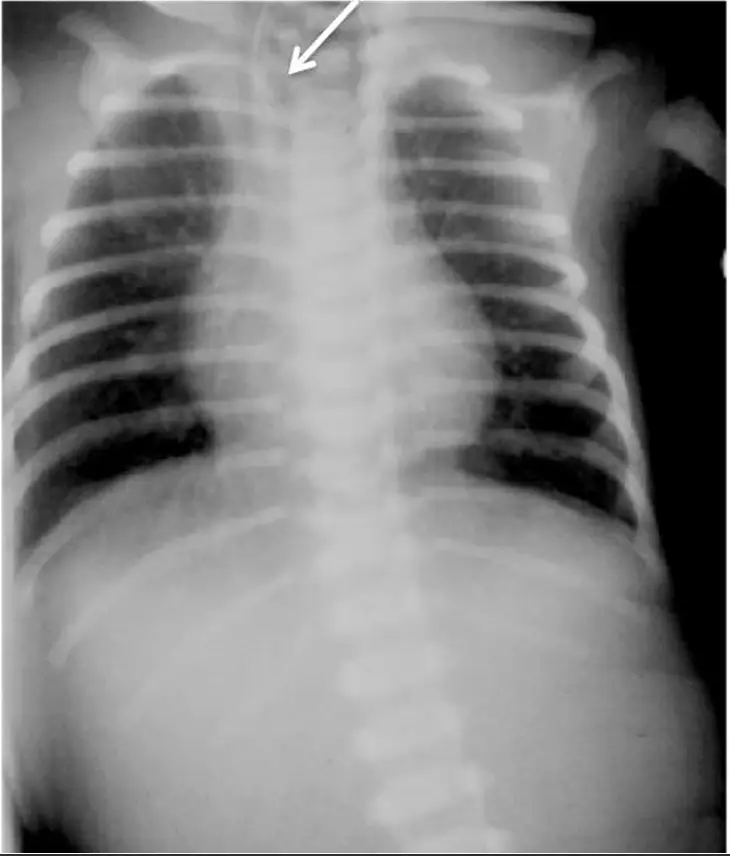

Esophageal Atresia X-ray: Radiographic Signs:

Esophageal Atresia X-ray: Other Cases: Radiological cases of Surgery It is a congenital condition that can be identified through radiographic findings. Key indicators include: What is Esophageal Atresia? It is a birth defect where a baby’s esophagus (food pipe) doesn’t connect properly to the stomach. Instead, it ends in a pouch, making swallowing impossible. This condition occurs […]